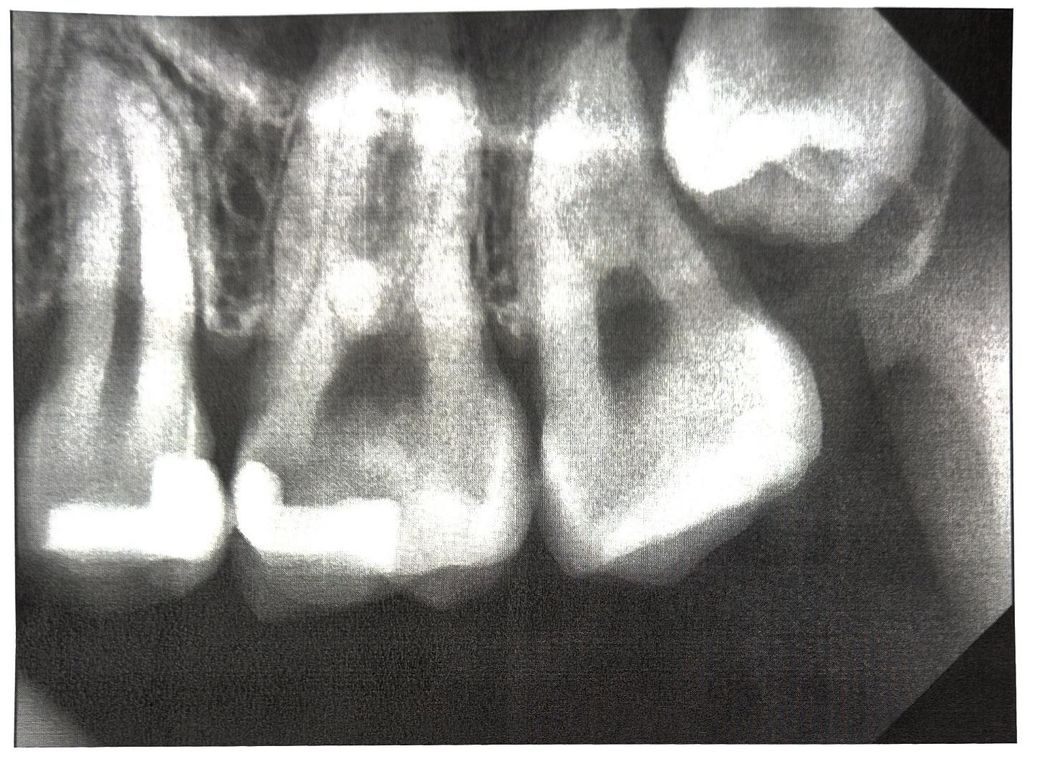

파노라마 사진은 치아전부가 다 나옵니다. 지금 사진은 치아 몇개만 보입니다. 원본이라면 치근단 사진입니다. 그러나 파노라마 사진을 자른 것일 수도 있습니다.

사진이 흐리지만 우측편에 턱관절 뼈의 양상이 살짝 보이는 것으로 보아 파노라마 가능성이 높습니다.

사진 화질이 몹시 안좋긴 합니다만 치근단 사진이 맞긴 한 것으로 보입니다. 오른쪽 위아래 모서리가 짤려있는게 특징입니다.

네 파노라마 사진 잘라서 확대했을 수도 있습니다. 해상도가 다소 낮아보입니다. 그게 아니라 진짜 치근단 사진이라면 필름 수현상, 초점 이상, 과노출 등으로 퀄리티가 낮은 사진입니다.